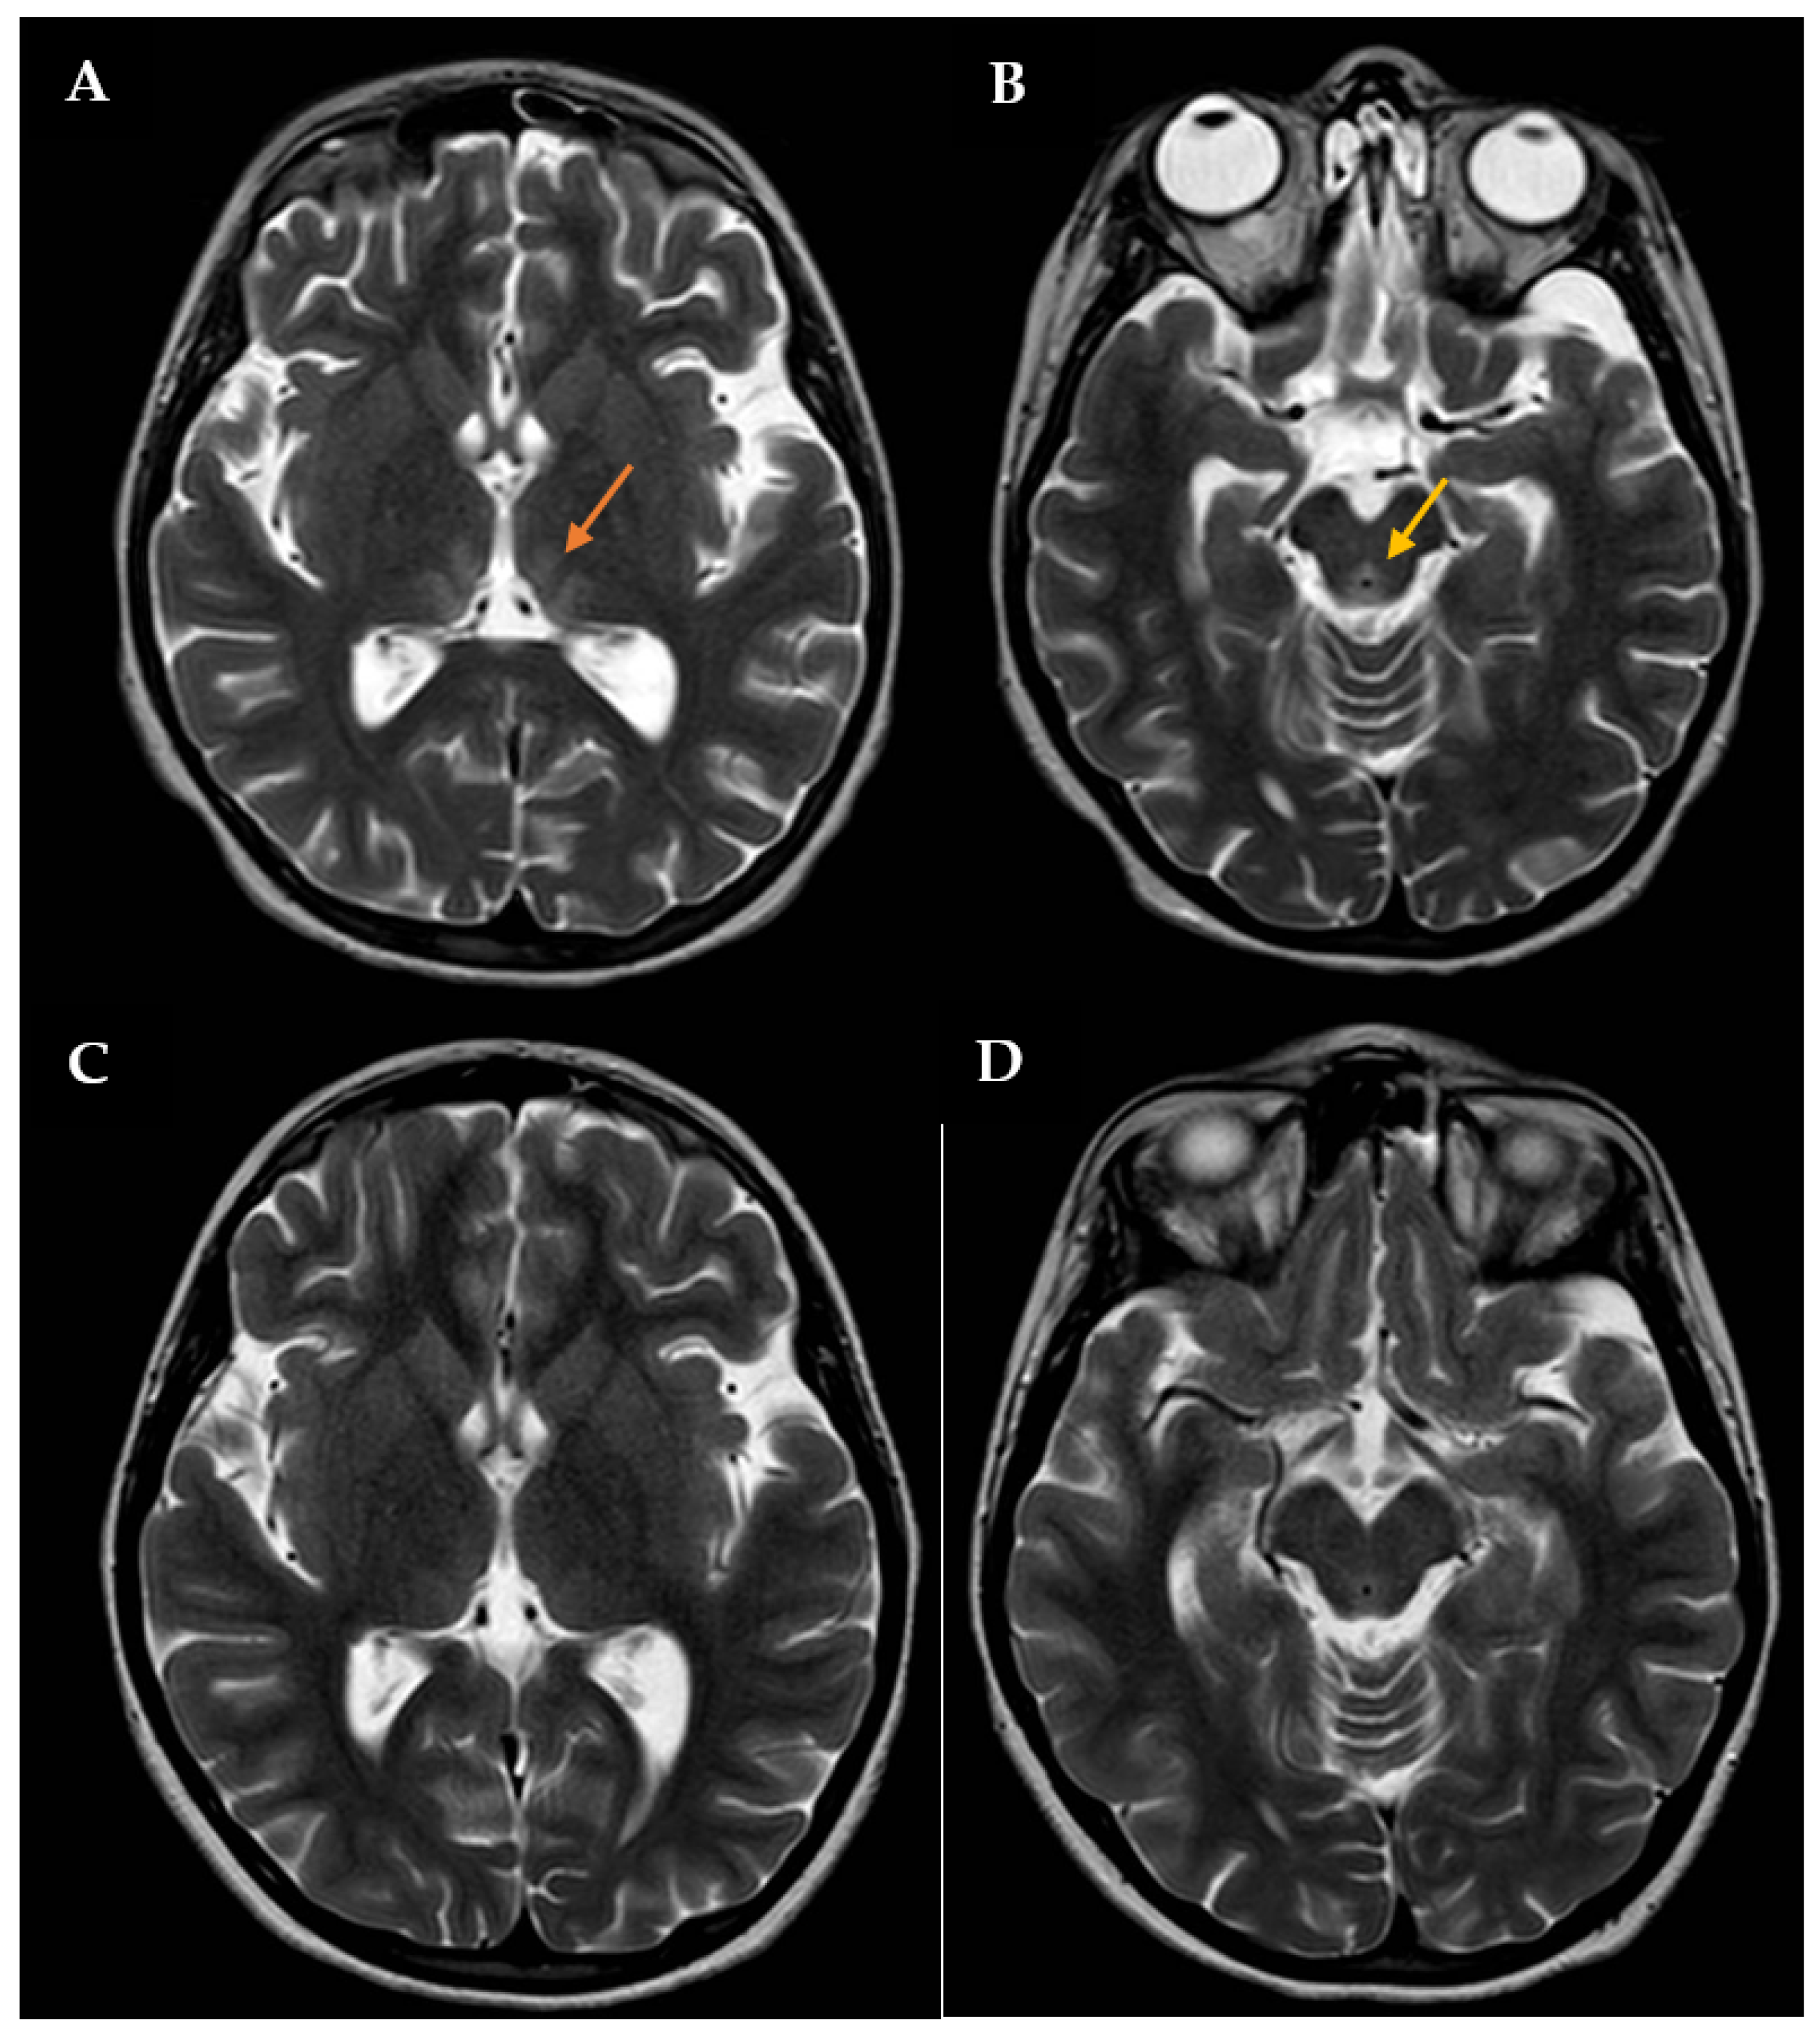

During this hospitalization, the patient’s condition actually deteriorated, requiring endotracheal intubation and intermittent positive pressure ventilation. The results of routine hematologic and biochemical measurements, including glucose, sodium, potassium, calcium, urea, creatinine, amylase, lipase, alanine aminotransferase, aspartate aminotransferase, gamma-glutamyl transpeptidase, alkaline phosphatase, and blood coagulation parameters, were all within normal limits. Cerebrospinal fluid analysis was also normal. The search for infectious agents, including human immunodeficiency virus and different neurotropic viruses, was completely negative. To rule out the autoimmune nature of such conditions, anti-nuclear, anti-DNAds, anti-onconeural, anti-aquaporine-4, anti-myelin oligodendrocyte glycoprotein, anti-myelin associated glycoprotein, and anti-ganglioside antibodies were also measured, with all being negative. An expanded screening for metabolic diseases and endocrinopathies was performed, with negative results. Brain computed tomography (CT) scan revealed low-density signal abnormalities in the paraventricular thalamic regions, while brain magnetic resonance imaging (MRI, Figure 1A,B) showed slight bilateral symmetrical T2 hyperintensity in the medial thalamic nuclei, along the walls of the third ventricle and in the periaqueductal region. Neuroradiological and clinical signs were consistent with WE. Intravenous therapy with thiamine was subsequently started (600 mg twice daily). The patient’s clinical condition improved four days after starting treatment. Therefore, the girl was extubated, and two days after, she was transferred to the Child Neuropsychiatry ward. At that time, the girl had both horizontal and vertical nystagmus, eyelid ptosis, and mild ataxic gait; she was also receiving enteral nutrition via nasogastric tube (900 kcal daily). The serum thiamine level was obtained 14 days after admission to the Pediatric Intensive Care Unit and confirmed to be low: 23 ng/mL (tested using Electro-ChemiLuminescence ImmunoAssay; normal reference: 32–95). Then, thiamine was administered per os (100 mg/day), as agreed upon with the nutritional counseling team.

Figure 1.

Brain MRI with contrast showing T2 signal hyperintensity involving the medial thalami (orange arrow in A) and the periaqueductal region (yellow arrow in B). The patient was initially treated with high-dose intravenous thiamine, then with oral thiamine on a daily basis. A new brain MRI showing a significant improvement in lesions was assessed one month after disease onset (C,D).

The patient had an almost complete resolution of her neurological symptoms, with persistence of mild nystagmus occurring only in extreme positions of the gaze and slight instability in static and dynamic equilibrium tests; the video-EEG revealed a normal organization of the patient’s cerebral electrical activity. She was discharged on 100 mg of oral thiamine and oral aripiprazole (increased to 2.5 mg twice a day), while outpatient CBT was also arranged. After approximately 1 month of thiamine therapy, a brain MRI showed a full resolution of the previously reported altered signals in the thalami along the walls of the third ventricle and periaqueductal areas (Figure 1C,D).